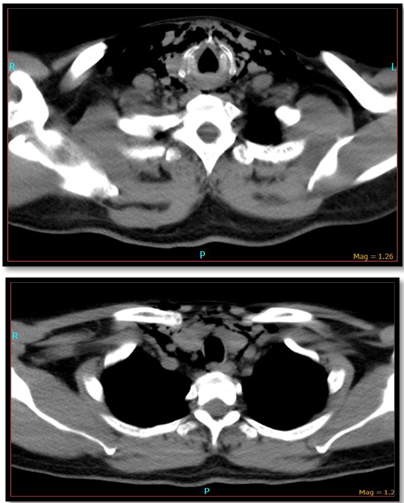

The second patient is a 58year male who came to the emergency room with alleged history of RTA following which he developed difficulty in swallowing and spitting out blood stained sputum. Examination revealed subcutaneous emphysema and tenderness over the laryngeal frame work. CT-neck plain showed extensive emphysema of neck with extension into the superior mediastinum (Figure 1) and fracture of thyroid cartilage at the midline with mild lateral displacement of the right side ala (Figure 2). He was admitted in the intensive care unit and was monitored for 24hours after which tracheostomy followed by neck exploration and laryngeal stabilization under general anesthesia was performed where in the fragmented thyroid cartilages were sutured. He was on ryles tube feed for 2months following which he was decannulated and ryles tube was removed.

Traumatic airway injuries are fortunately rare. Though injuries can be obvious and initial management straightforward, the diagnosis can be difficult. Laryngeal trauma could either be a blunt trauma or a penetrating injury. It has been reported in US that less than 1 percent of all trauma involves the larynx.7 In the United States, the incidence of both forms of injury in the 1980s ranged from one in 5,000 emergency visits8 and one in 30,000 emergency visits in the 1990s.5 Concurrent injury to the pharynx and/or esophagus is infrequent in both penetrating and blunt laryngeal trauma.9 The most common finding in these patients has been dysphonia and pain/tenderness of the larynx.5 CT imaging is beneficial in patients with a significant history of blunt force trauma to the anterior neck with or without significant abnormal findings on physical examination, particularly with dysphonia or hemoptysis, and if the condition and continuity of the endolarynx and trachea is not observable due to edema or hematoma.3 Video stroboscopic laryngoscopy provides an excellent assessment of vocal fold mobility and integrity, and potential reversibility of injuries.10 Stroboscopic examination is also useful for the assessment of recovery. The timing of early surgical management ranges from within 24hours to several days. However it has been reported by Herbert Harris in 1965 and 1970 that surgery is beneficial within 24hours of injury11,12 Following acute airway management, laryngeal injuries are managed based on the severity of injury and specific elements of each lesion. A classification and treatment protocol has been described by Schaefer5 Group I laryngeal traumas demonstrate only minor laryngeal edema or lacerations. Typically, this group can be treated with steroids, antibiotics, antireflux therapy, close observation. Group II includes more demonstrative edema or hematomas without exposed cartilage. Diagnostic endoscopy and tracheostomy are frequently indicated for this group. Group III laryngeal traumas demonstrate massive edema or large mucosal lacerations. Conservative management includes anti inflammatory, anti relux, antibiotics and corticosteroids. Surgical management includes tracheostomy, direct laryngoscopy and oesophagoscopy open operative interventions and laryngeal stents (Figures 3-7).

Figure 7CT- Neck showed extensive subcutaneous emphysema with extension into posterior pharyngeal space and left posterior neck space.